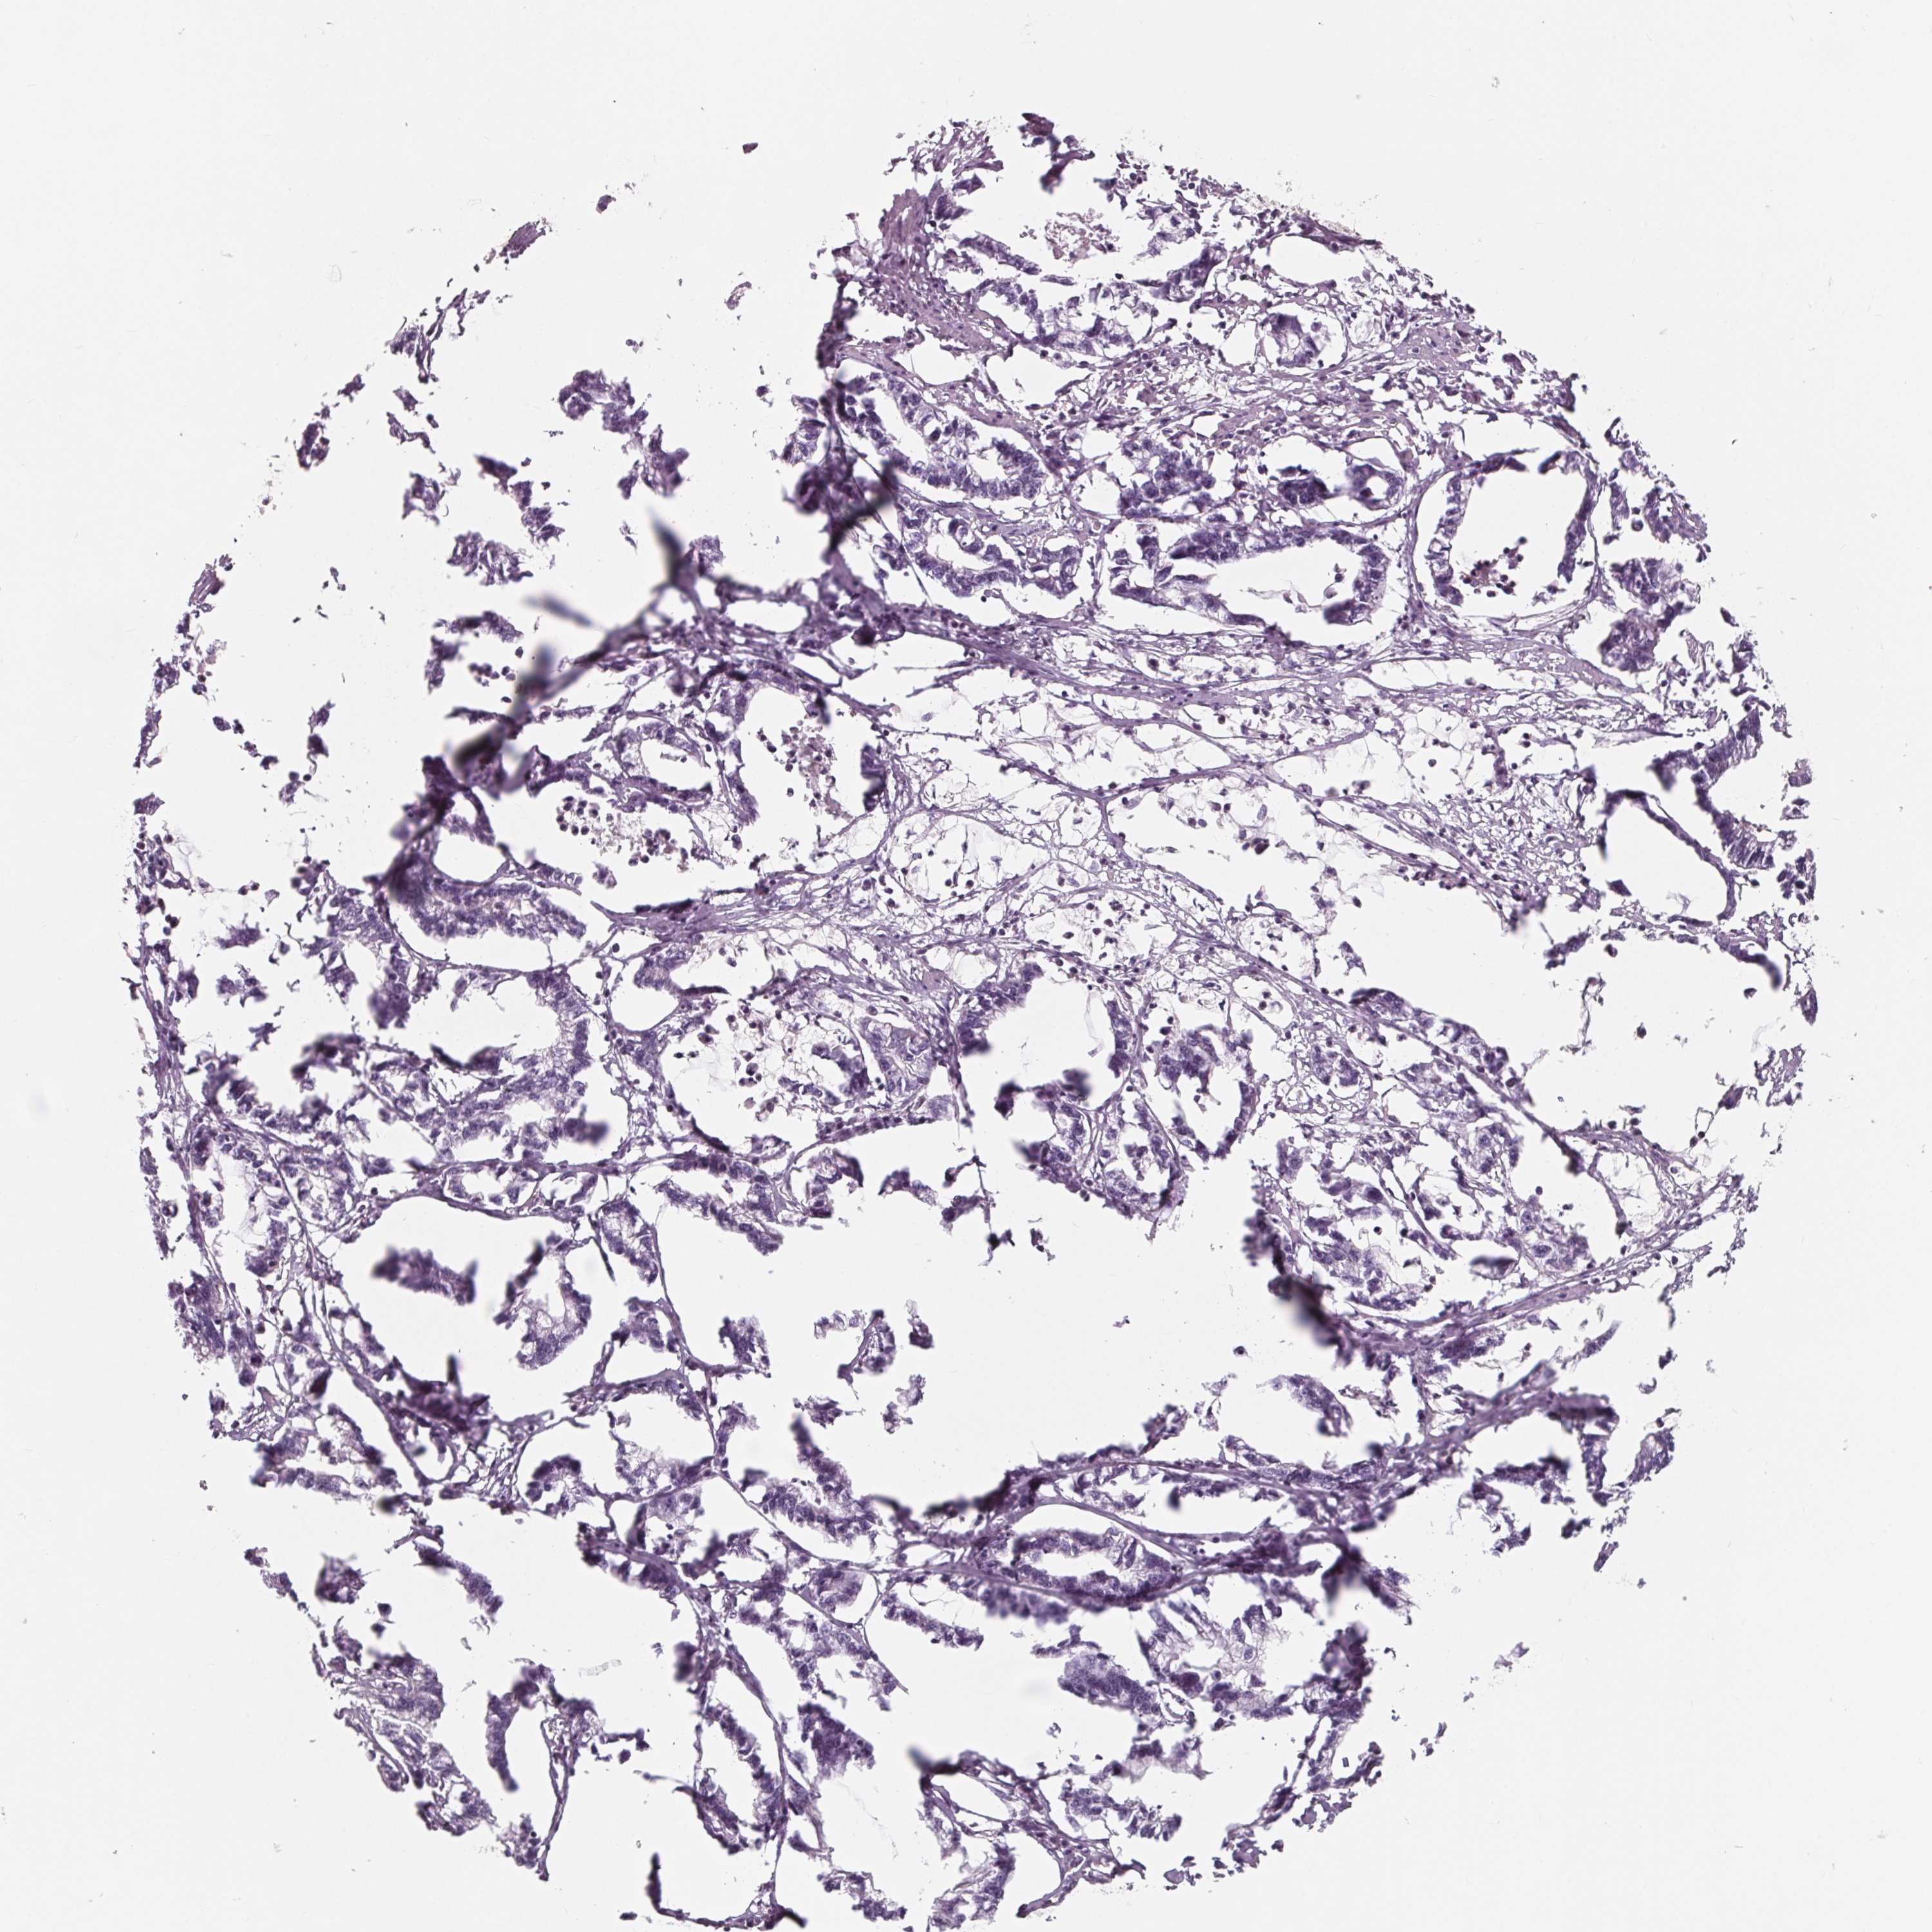

STOMACH CANCER - Protein expressioni

A mouse-over function shows sample information and annotation data. Click on an image to view it in a full screen mode. Samples can be filtered based on level of antibody staining by selecting one or several of the following categories: high, medium, low and not detected. The assay and annotation is described here.

Note that samples used for immunohistochemistry by the Human Protein Atlas do not correspond to samples in the TCGA dataset.

Antibody stainingi

Antibody staining in the annotated cell types in the current human tissue is reported as not detected, low, medium, or high, based on conventional immunohistochemistry profiling in selected tissues. This score is based on the combination of the staining intensity and fraction of stained cells.

Each image is clickable and will lead to virtual microscopy that enables deeper exploration of all samples and also displays staining intensity scores, fraction scores and subcellular localization as well as patient and tissue information for each sample.

Antibody HPA035346

Antibody HPA061395

Adenocarcinoma, NOS